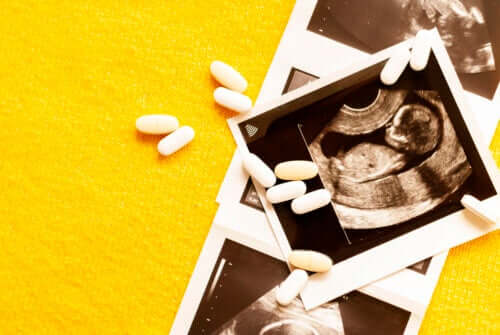

Pour le réaliser, le médecin réalise une échographie abdominale avec un échographe haute résolution et réalise ainsi une mesure plus précise. Lors de l’examen, le professionnel doit rechercher un plan latéral, qui lui permet d’évaluer la longueur craniocaudale (CCL) de l’enfant, qui est la distance de la tête au coccyx. Idéalement, le fœtus doit mesurer entre 45 et 84 mm pour que l’examen se déroule correctement.

Une fois l’appareil localisé, l’épaisseur maximale du pli nucal est mesurée. En particulier l’ombre (ou la translucidité) qui subsiste entre la peau et les tissus mous qui recouvrent la colonne cervicale. Normalement, cette épaisseur est inférieure à 3 mm.

Lorsque la clarté nucale est supérieure à cette valeur, elle peut être associée à un risque accru de certaines maladies génétiques, comme le syndrome de Down.